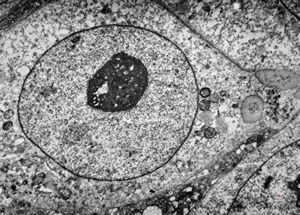

F,49y. | purulent meningitis- meningococcal v.s.

F,49y. | purulent meningitis- meningococcal v.s.

F,49y. | purulent meningitis- meningococcal v.s.